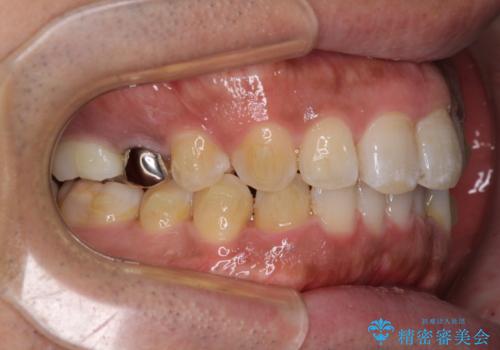

レントゲン撮影により、右上奥歯が折れていることが分かりました。

患者様自身も何となく違和感を覚えていたとのことで、インプラント補綴治療を行うこととしました。

破折して抜歯が必要となった歯の後ろの歯は、根管治療が必要な状態であったので、根管治療を行い、矯正治療後にインプラント部の補綴治療と同時にセラミッククラウンを装着しました。

矯正治療以外に費用負担がかかることになりましたが、気になるところ全てを処置することができ、患者様には大変満足していただきました。